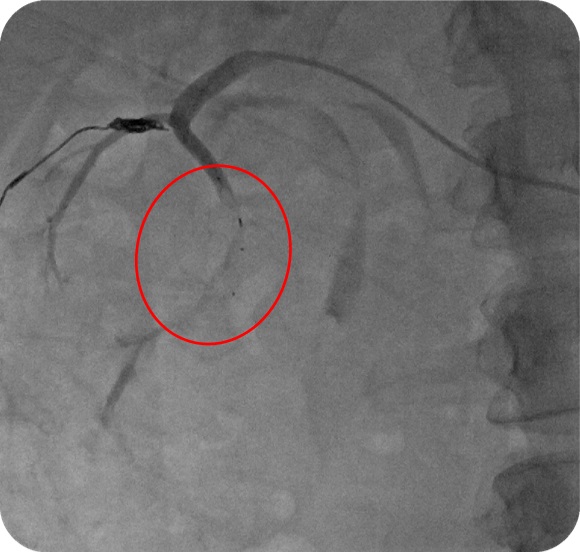

微导管应用:血管塞